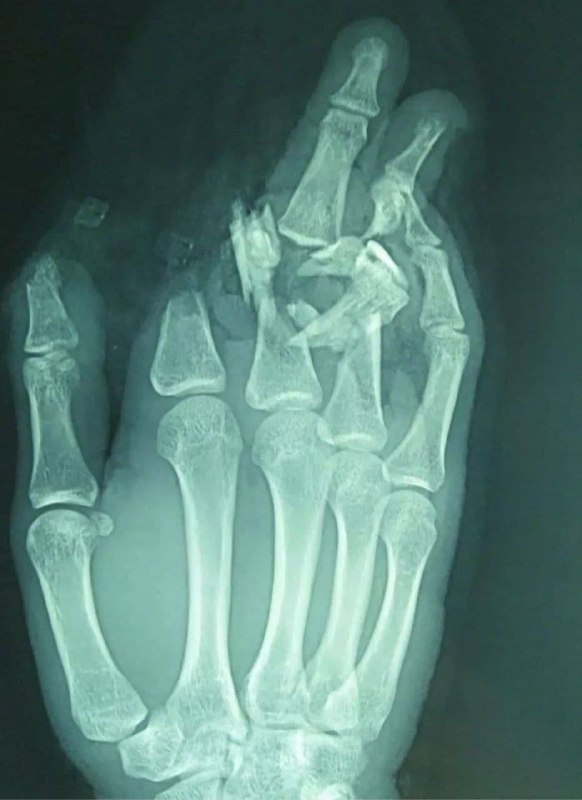

Жесть Категория